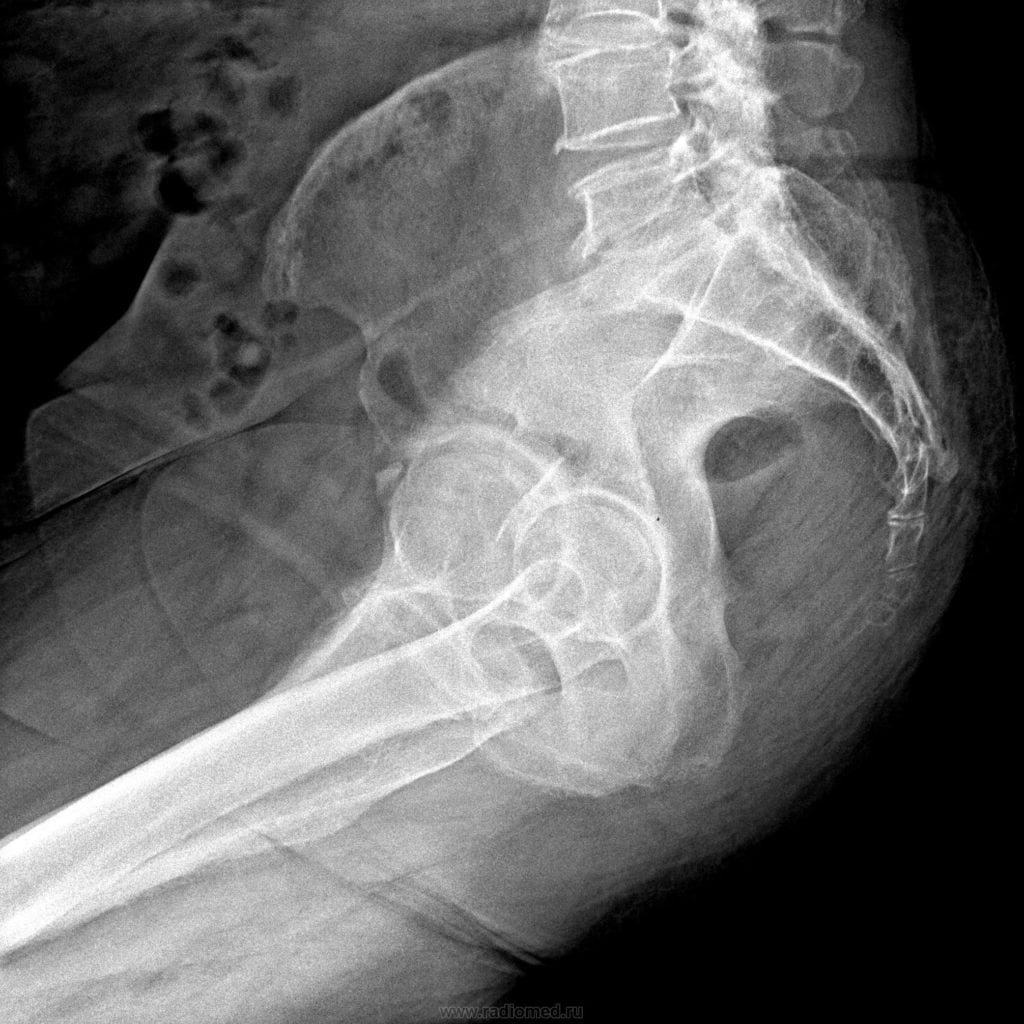

Последствия падений и ушибов в области поясницы могут вызывать боль в копчике. Не стоит игнорировать этот симптом. Любая боль сигнализирует о патологическом процессе и требует выявления причины с последующим лечением.

Болезненные симптомы в копчике не всегда связаны с незначительными травмами, которые можно устранить народными средствами. Если обследование показывает, что болевой синдром в копчике вызван ушибом или является послеоперационным симптомом, врач может рекомендовать использование наружных мазей, растираний настойками, гимнастику или лечебные ванны.

Однако свищи, кисты или переломы в этой области не лечатся только растираниями и компрессами. Необходим длительный курс лечения с применением противовоспалительных и обезболивающих препаратов, чтобы избежать ухудшения состояния или неправильного сращения поврежденных участков позвоночника.